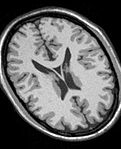

The Interactive Editor can be used to create and edit label maps for quantitative analysis and surface model generation (Steve Pieper)

EM Segmenter, simple version (Kilian Pohl)

Fast Marching segmentation (Andriy Fedorov)

Robust Statistical Segmentation (Yi Gao)